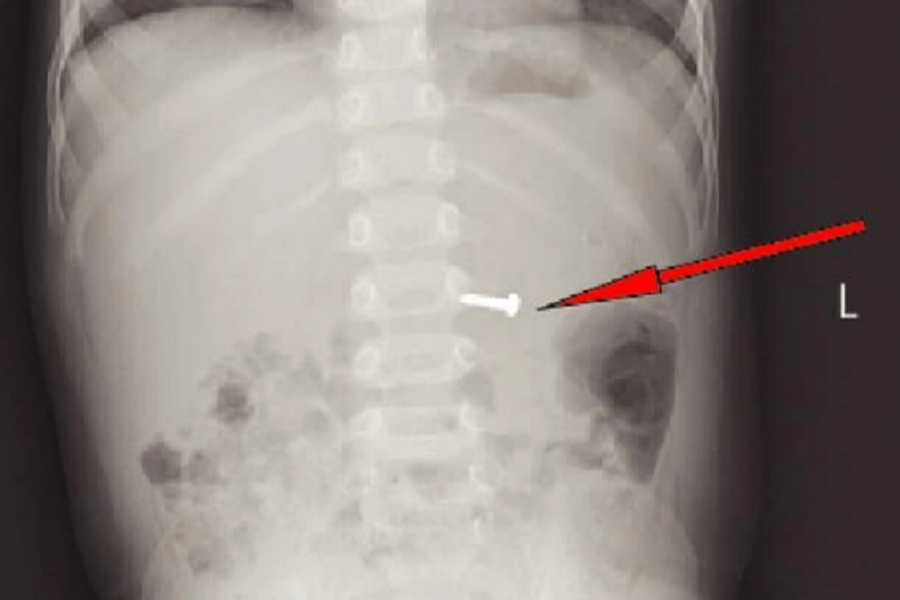

Trong lúc chơi đùa tại nhà, một cháu bé 19 tháng tuổi ở Ninh Bình đã nuốt phải một chiếc ốc vít sắc nhọn, dài 1,5cm nên phải đưa đi bệnh viện cấp cứu.

Ngày 23/11, tin từ Bệnh viện Sản nhi Ninh Bình cho biết, các bác sĩ vừa nội soi cấp cứu thành công cho bệnh nhi nuốt phải dị vật là chiếc ốc vít bằng kim loại.

Trước đó, trong lúc chơi đùa tại nhà, cháu P.G.H. (19 tháng tuổi, trú TP Tam Điệp), đã nuốt phải một dị vật kim loại là chiếc ốc vít sắc nhọn nên được đưa đi bệnh viện cấp cứu.

Dựa trên kết quả khám, chụp X-quang, các bác sĩ đã gây mê nội soi thực quản dạ dày tá tràng cấp cứu. Sau 15 phút can thiệp, ê-kíp đã lấy ra chiếc ốc vít dài 1,5cm với một đầu sắc nhọn đã găm tại thân vị của dạ dày. Sau khi gắp được dị vật ra ngoài, sức khỏe cháu bé đã ổn định và được cho xuất viện.